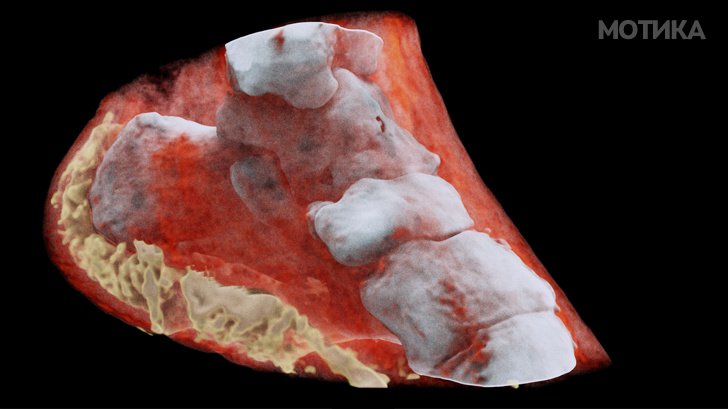

10. Сликата на глуждот направена со спектрален скенер во боја.